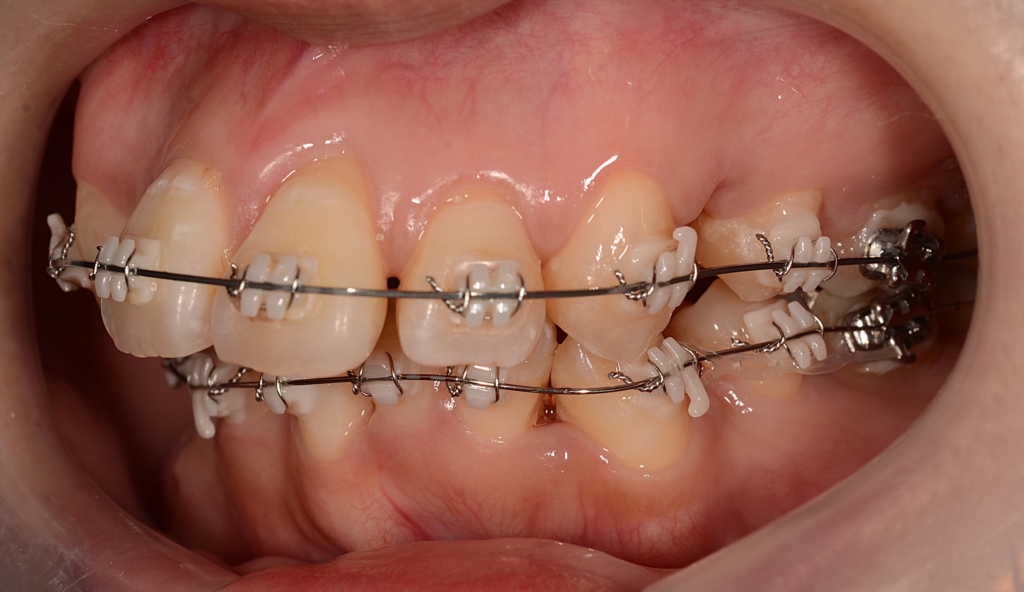

【治療開始】 (写真は4か月経過時点です)

マルチブラケットシステム(スタンダードtype)で矯正を開始

アンカースクリュー

(上顎の口蓋に2本使用)